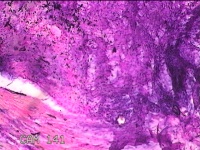

会阴部结节

性别

男

年龄

34岁

临床诊断

会阴部良性肿瘤

一般病史

发现会阴部结节1周。

标本名称

大体所见

灰白粉红色组织1.3x1.2x0.3cm一块,表面光滑,切面灰白粉红色。质软。